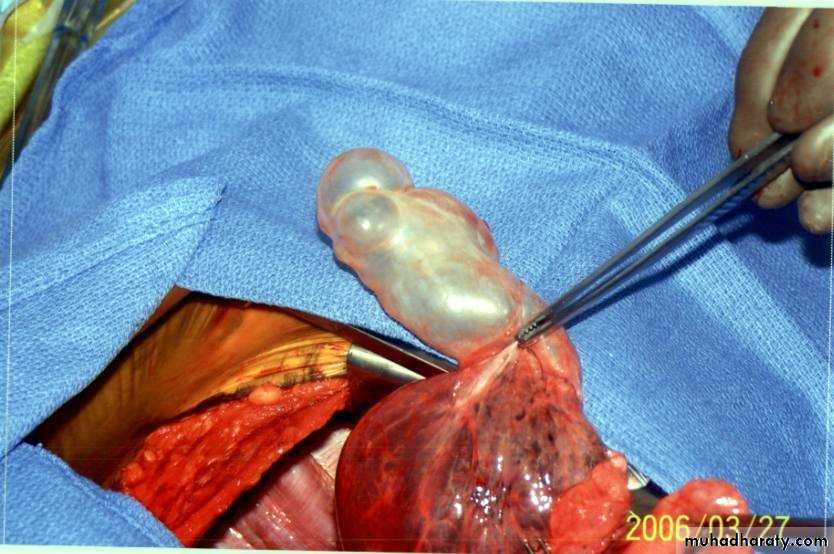

EmphysemaBullae (large air-filled spaces) form in some patients.

Bullectomy for younger patients in whom large bullae compress relatively normal lung tissuesLung volume reduction surgery (LVRS) for highly selected patients with;